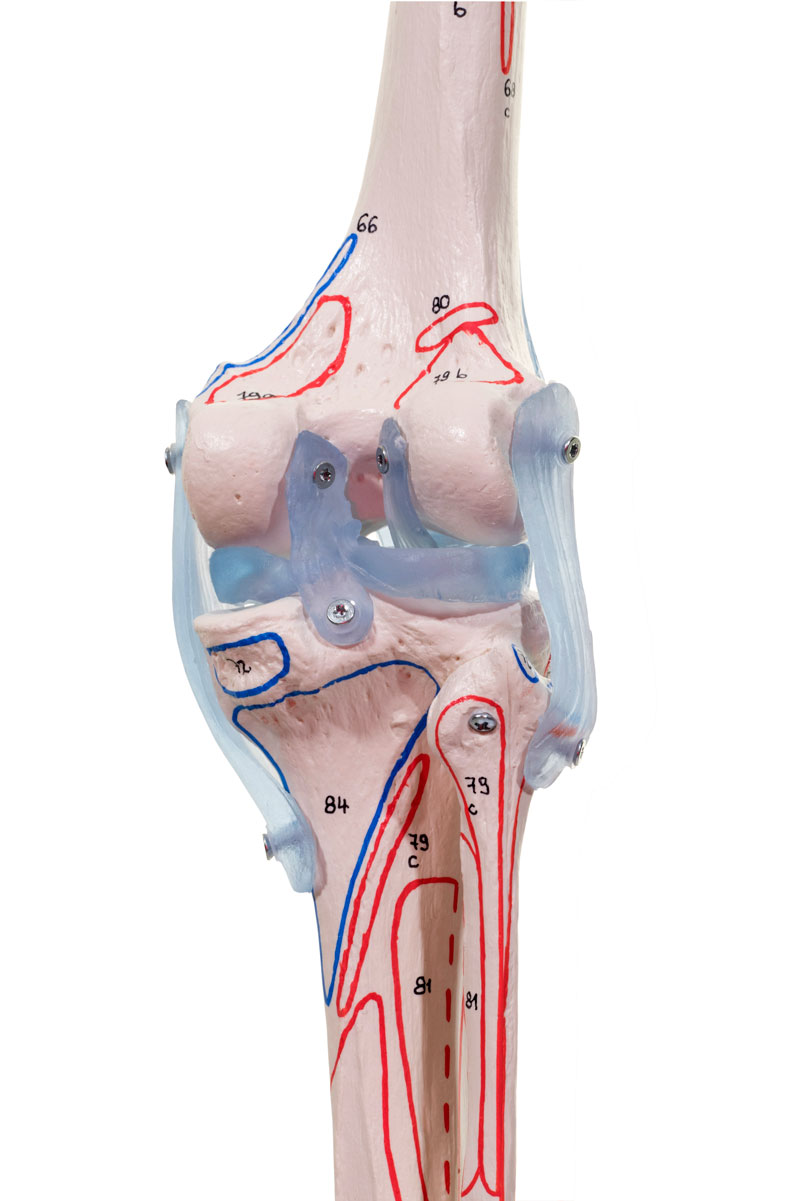

Ligaments

Avec ligaments